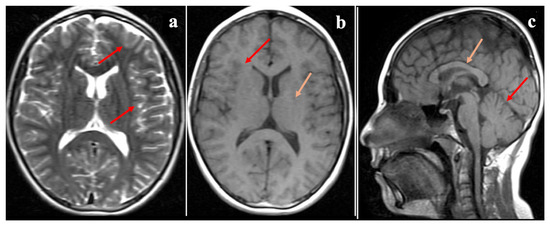

Further neurological assessments revealed that both affected siblings demonstrated impaired cognitive function but were able to follow simple commands and communicate effectively. Muscle strength in the upper and lower extremities was preserved, sensory responses were normal, and deep tendon reflexes were hypoactive. There were no signs of extremity spasticity, pathological reflexes, or seizure activity. The Romberg test was positive, and both dysarthria and dysdiadochokinesia were present. Cranial MRI of the elder sibling (P1), performed at the age of 20, showed mild cerebellar atrophy (Figure 1), whereas the MRI of the younger sibling (P2), obtained at the age of 12, revealed no structural abnormalities (Figure 2). Eye movements were normal in both cases, and no tongue fasciculations or aphasia were observed. Additionally, plasma creatine kinase (CK) levels were within normal limits for both patients.

Figure 1.

Cranial MR images of the index patient (Proband 1, P1) at 20 years of age. Cranial MR images of the index patient (Proband 1, P1) at 20 years of age. (a) T2-weighted axial image shows normal cerebral sulci (red arrows) and basal ganglia (orange arrow). (b) T1-weighted sagittal image reveals mild cerebellar atrophy (red arrow). (c) T1-weighted axial image shows normal cerebral sulci (red arrows) and basal ganglia (orange arrow). (d) T2-weighted coronal section demonstrates normal ventricular volume (red arrows).